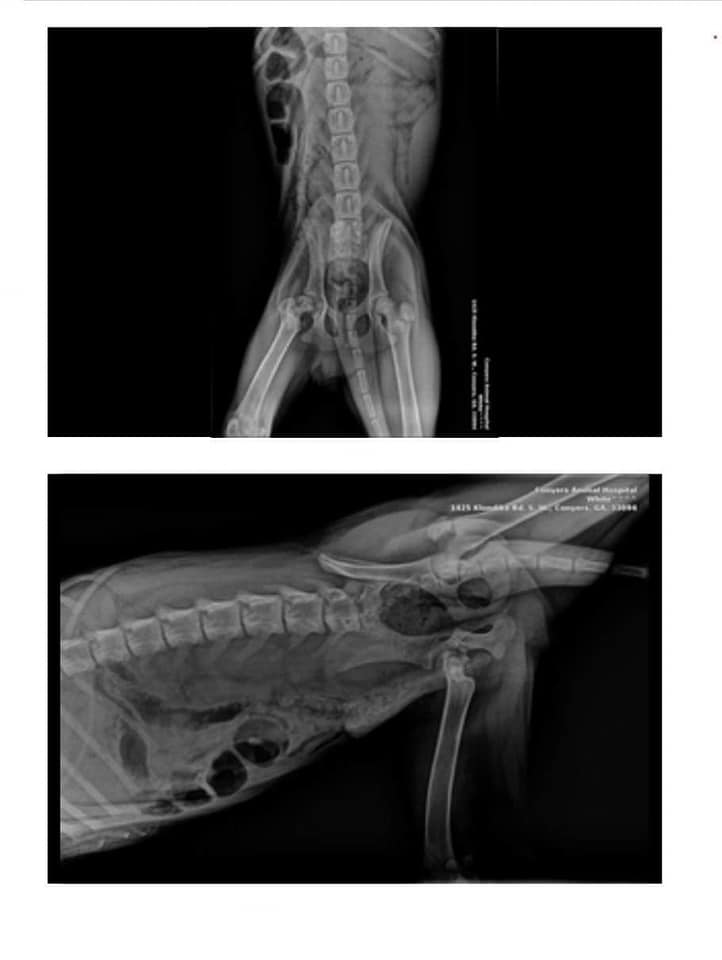

She needed to be neutered to not only protect her from future pregnancies but also to reduce her likelihood of getting certain diseases, womb infections and tumours, such as mammary tumours, which are less likely to form the earlier a cat is neutered. She had also needed dental surgery to remove five teeth which would have made eating difficult and painful.